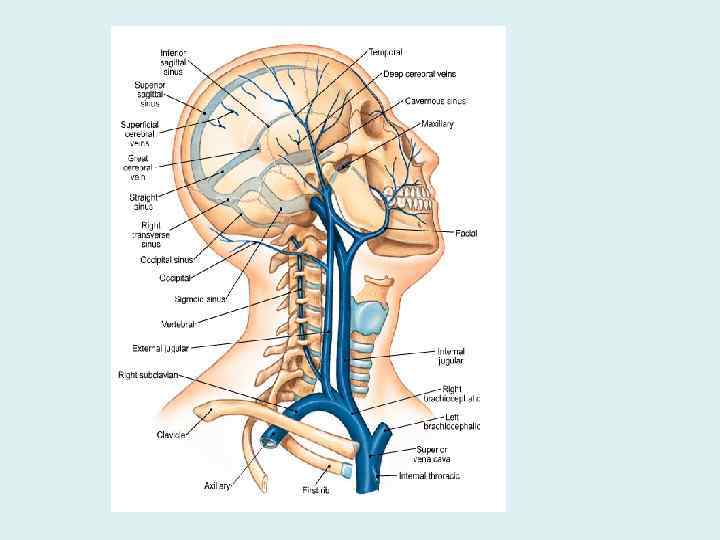

Внутренняя яремная вена • Собирает кровь от головы и шеи, из бассейна наружной и внутренней сонных и позвоночных артерий • Исток: сигмовидный синус • Притоки: внутричерепные и внечерепные

Внутричерепные притоки • • • Синусы твердой мозговой оболочки диплоические вены, глазные вены, вены лабиринта, мозговые вены, вены оболочек

Синусы твердой мозговой оболочки

Синусы твердой мозговой оболочки • Стенки синусов сращены с твердой оболочкой, • не спадаются, • обеспечивают свободный отток крови от мозга • Это вены волокнистого типа

Внечерепные притоки • • • Лицевая вена Позадичелюстная вена Глоточные вены Язычная вена Верхние щитовидные вены Средняя щитовидная вена

Анастомозы внутричерепных и внечерепных притоков • Вены выпускники, диплоические вены соединяют синусы с венами свода черепа • Крыловидное сплетение соединяет средние оболочечные вены с позадичелюстной и лицевой венами

Анастомозы внутричерепных и внечерепных притоков • Глазная вена соединяет пещеристый синус с лицевой веной